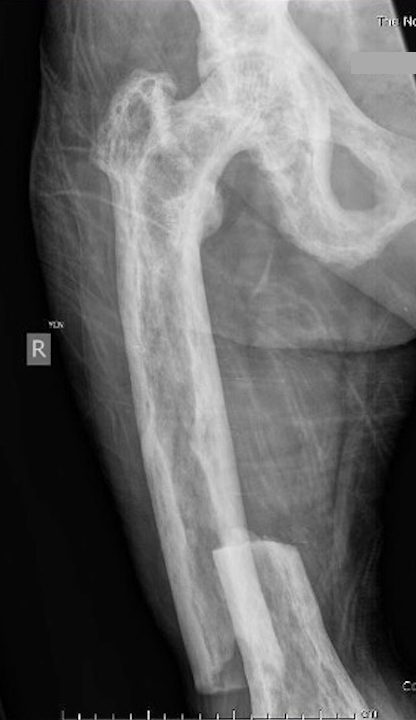

Tibia

Tibia deformity - sabre tibia

Fracture

Issues

Paget's fractures likely have normal healing capacity

Hard bone - difficult entry points

Bleeding

Deformity - may require osteotomy prior to IM nails